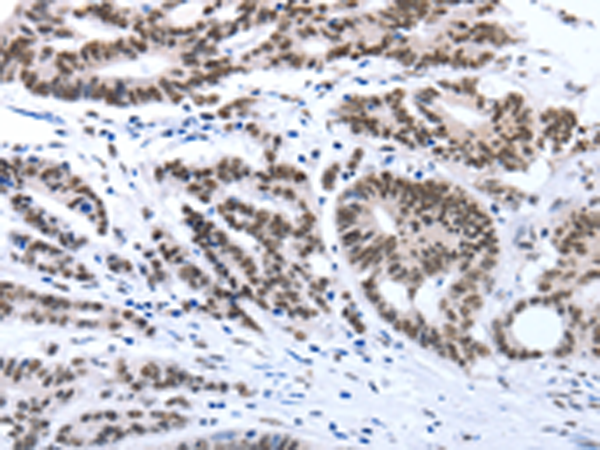

分类: 科研抗体货号: P11133别名: MTK1; MEKK4; MAPKKK4; PRO0412应用: IHC反应种属: Human